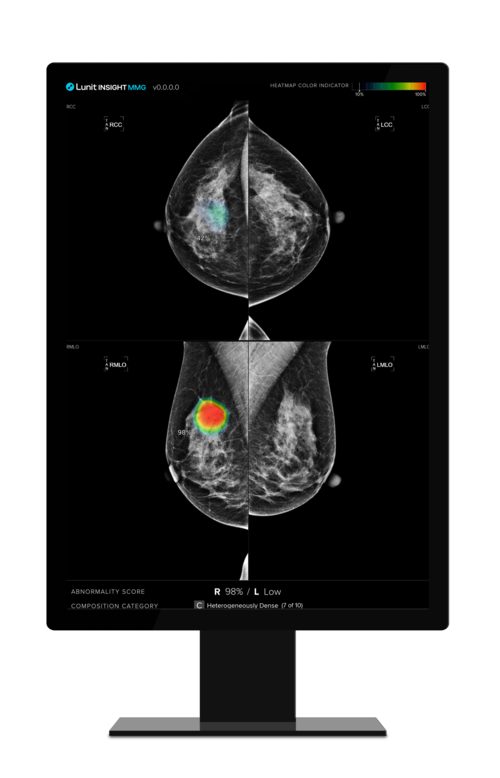

- ▲ 유방촬영술 AI(인공지능) 영상진단 솔루션 '루닛 인사이트 MMG' 운용화면.ⓒ루닛

루닛이 유방촬영술 AI(인공지능) 영상진단 솔루션 '루닛 인사이트 MMG'가 보건복지부 산하 한국보건의료연구원(NECA)으로부터 '평가 유예 신의료기술'로 선정됐다고 16일 밝혔다.루닛 인사이트 MMG는 AI 기반 영상 판독 보조 소프트웨어 최초로 신의료기술로 분류돼 평가 유예를 받았다.루닛은 방대한 양의 글로벌 임상자료를 제출해 영상 판독 보조 소프트웨어로는 이례적으로 현저한 진단능력 향상 및 오류감소 효과 등의 가능성을 인정받아 신의료기술 평가 대상에 이어 이번 평가 유예에 선정됐다고 설명했다.신의료기술 평가 유예 제도는 조기 도입이 필요한 새로운 의료기술에 대해 평가를 유예함으로써 조기에 의료현장에서 비급여로 사용할 수 있도록 허용하며 비급여 상한액의 제한을 두지 않는다.그동안 영상 판독 보조 소프트웨어는 의사의 판독 행위와 사용목적과 대상이 유사하다는 이유로 기존 기술로 분류되거나 혁신의료기술로 평가받았다.루닛은 이번 신의료기술 평가 유예를 기반으로 지속적인 임상 근거를 창출하고 향후 신의료기술 평가를 거쳐 건강보험의 정식 등재를 추진할 계획이다.루닛은 올 3분기부터 최대 5년간 비급여로 루닛 인사이트 MMG를 국내 의료현장에 진입시킬 수 있게 됐다.지난달 비급여 시장에 새로 진입한 흉부 엑스레이 AI 영상분석 솔루션 '루닛 인사이트 CXR'까지 더하면 루닛은 국내 유방암 및 폐암 진단 시장에서 유의미한 결과를 올릴 수 있을 것으로 예상된다.글로벌 시장조사기관 모더 인텔리전스에 따르면 국내 유방암과 폐암 검진 및 진단 시장은 각각 1200억원과 2800억원 수준이다.서범석 루닛 대표는 "AI 영상진단 솔루션이 의료분야 신기술로서 건강보험 정식 등재 가능성이 확인된 만큼 앞으로도 암 조기진단을 통해 인류 건강에 기여하는 혁신 제품 개발에 앞장서겠다"고 말했다.